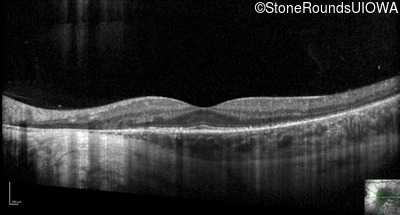

Optical Coherence Tomography - Right - 20/20

Exemplar / OCT Stack

Optical Coherence Tomography - Left - 20/20